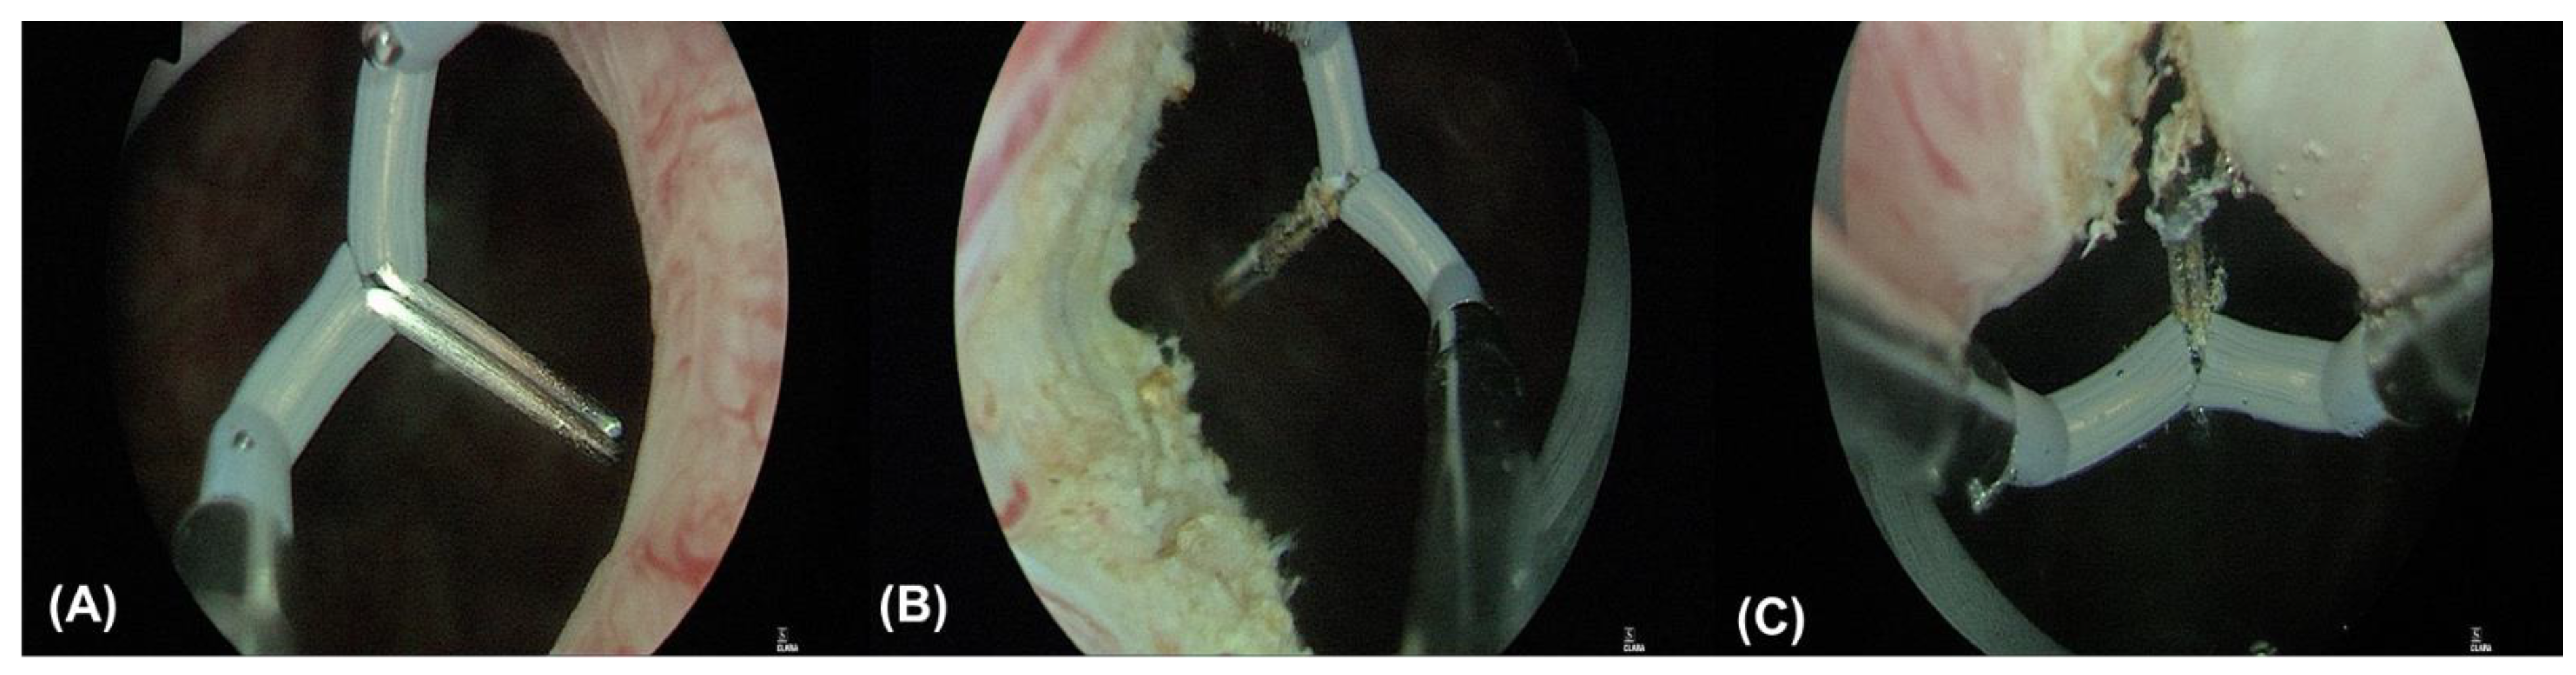

5.2. A Novel Treatment: Surgical Treatment with a Combination of Transvaginal Ultrasound-Guided BoNT-A Injection and TUI-BN